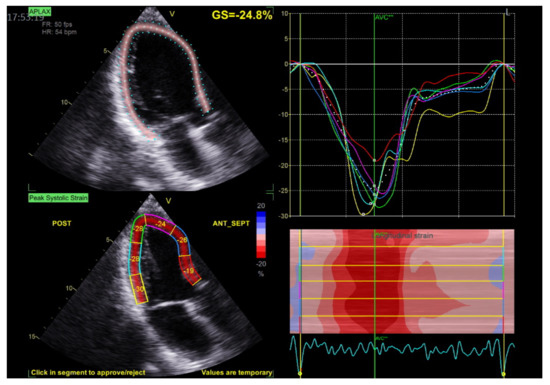

2.3. Echocardiography

- Voigt, J.-U.; Pedrizzetti, G.; Lysyansky, P.; Marwick, T.H.; Houle, H.; Baumann, R.; Pedri, S.; Ito, Y.; Abe, Y.; Metz, S.; et al. Definitions for a Common Standard for 2D Speckle Tracking Echocardiography: Consensus Document of the EACVI/ASE/Industry Task Force to Standardize Deformation Imaging. J. Am. Soc. Echocardiogr. 2015, 28, 183–193. [Google Scholar] [CrossRef]

- Leitman, M.; Lysiansky, M.; Lysyansky, P.; Friedman, Z.; Tyomkin, V.; Fuchs, T.; Adam, D.; Krakover, R.; Vered, Z. Circumferential and longitudinal strain in 3 myocardial layers in normal subjects and in patients with regional left ventricular dysfunction. J. Am. Soc. Echocardiogr. 2010, 23, 64–70. [Google Scholar] [CrossRef]

- Belghiti, H.; Brette, S.; Lafitte, S.; Reant, P.; Picard, F.; Serri, K.; Courregelongue, M.; Dos Santos, P.; Douard, H.; Roudaut, R.; et al. Automated function imaging: A new operator-independent strain method for assessing left ventricular function. Arch. Cardiovasc. Dis. 2008, 101, 163–169. [Google Scholar] [CrossRef]